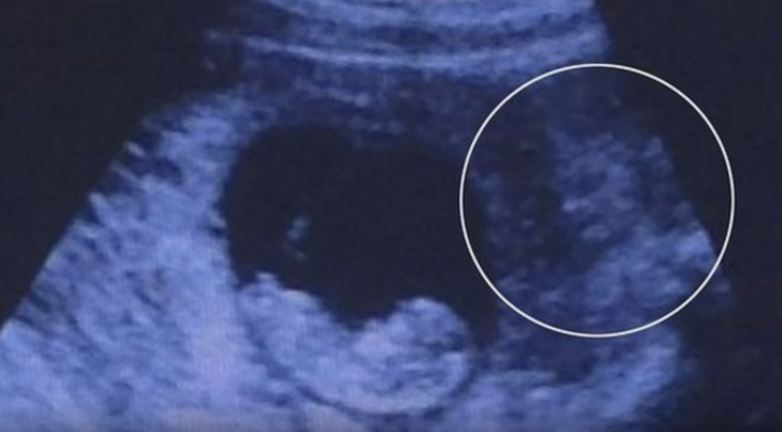

Scary Picture Of Unborn Child, Seen A Devil Beside It